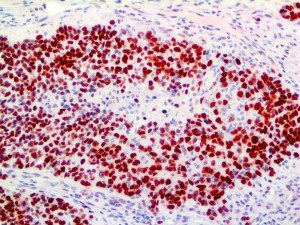

It is the ICU physician who is most likely to witness one of the deadliest manifestations of the abnormal immunological response, the cytokine storm syndrome (CSS). This response is also referred to by some as the cytokine release syndrome (CRS). CSS is characterized by continuous activation and expansion of macrophage and lymphocyte populations, which secrete large amounts of cytokines, causing the cytokine storm. This massive cytokine release is akin to hemophagocytic lymphohistiocytosis (HLH) disease, a syndrome characterized by initial unchecked and persistent activation of cytotoxic T lymphocytes and NK cells.

Clinical and laboratory manifestations of HLH include fever, enlarged liver and/or spleen, neurologic dysfunction, coagulopathy, liver dysfunction, cytopenias (i.e., low levels of erythrocytes, leukocytes, and/or platelets), hypertriglyceridemia, hyperferritinemia, hemophagocytosis, and eventually diminished NK cell activity as the immune system becomes progressively paralyzed. HLH can be familial (primary HLH) or secondary to another disease process (sHLH), such as rheumatic disease, in which it is referred to as macrophage activation syndrome (MAS, characterized by elevated ferritin).